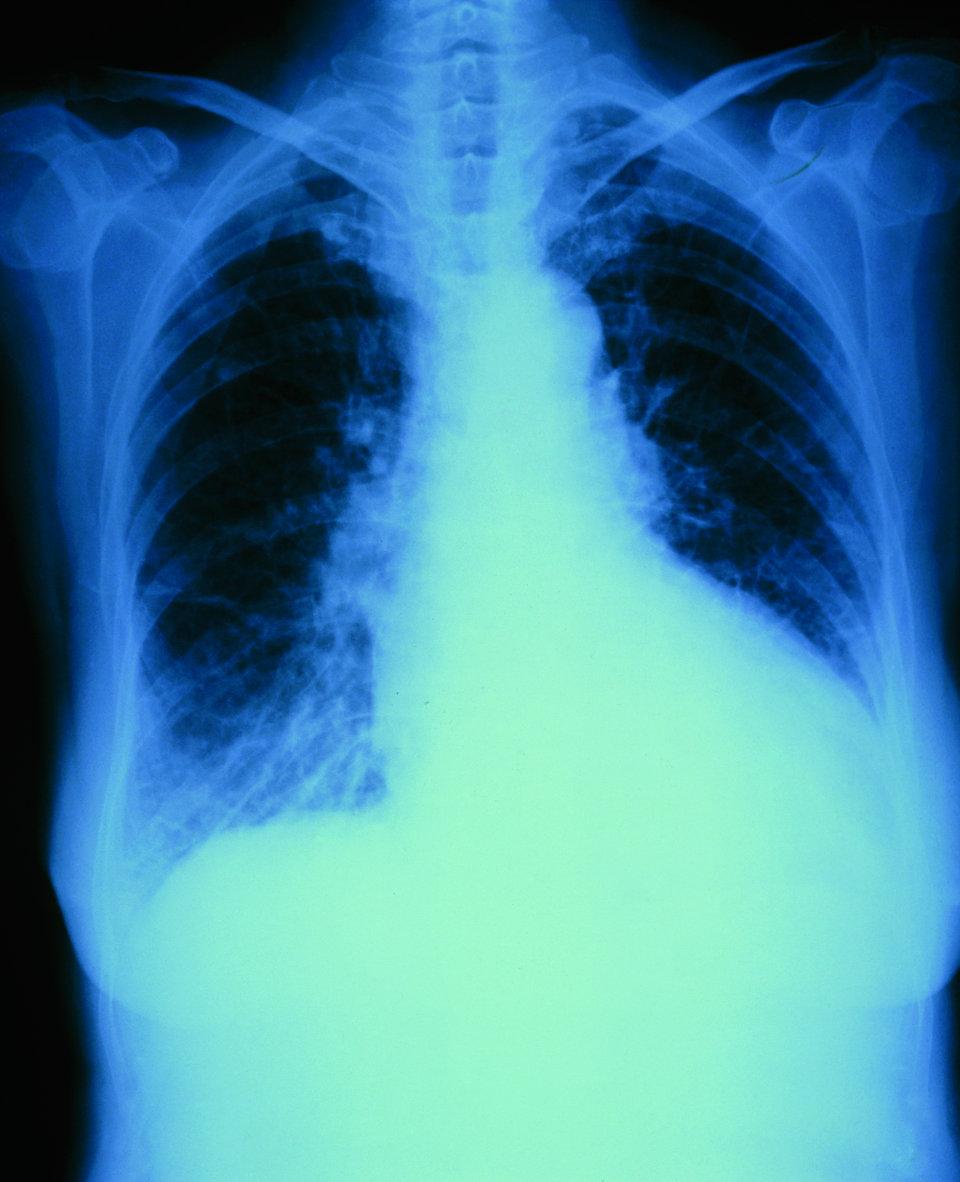

Wird die Pneumonie durch Pneumokokken oder Influenzaviren ausgelöst, steigt das kardiale Risiko um das Sechs- bis Zwölffache. Wird die Pneumonie durch Pneumokokken oder Influenzaviren ausgelöst, steigt das kardiale Risiko um das Sechs- bis Zwölffache. © Tatiana Shepeleva – stock.adobe.com

Bei jedem vierten hospitalisierten CAP-Patienten kommt es zu kardialen Komplikationen, am häufigsten zu einer dekompensierten oder neu aufgetretenen Herzinsuffizienz. Bei jedem vierten hospitalisierten CAP-Patienten kommt es zu kardialen Komplikationen, am häufigsten zu einer dekompensierten oder neu aufgetretenen Herzinsuffizienz. © Science Photo Library